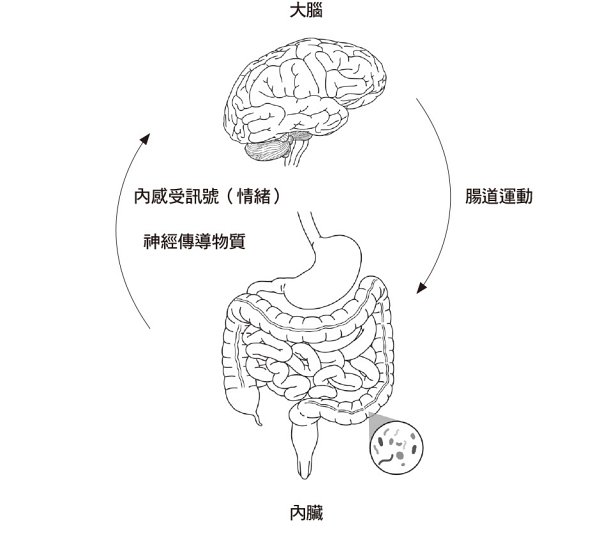

另外,腸胃是身體中最敏銳的部位,往往能最早察覺人際關係中的矛盾,或識別對個人生活可能造成威脅的潛在危險人物;而大腦中最先感知胃腸所發出的內感受訊號,並將之處理為所謂「情緒」訊息的部位,則是mPFC-ACC神經網路。因此mPFC-ACC可以說是在培養和發揮社交能力上非常重要的神經網路。對此,我們將會在第八章中詳細探討。